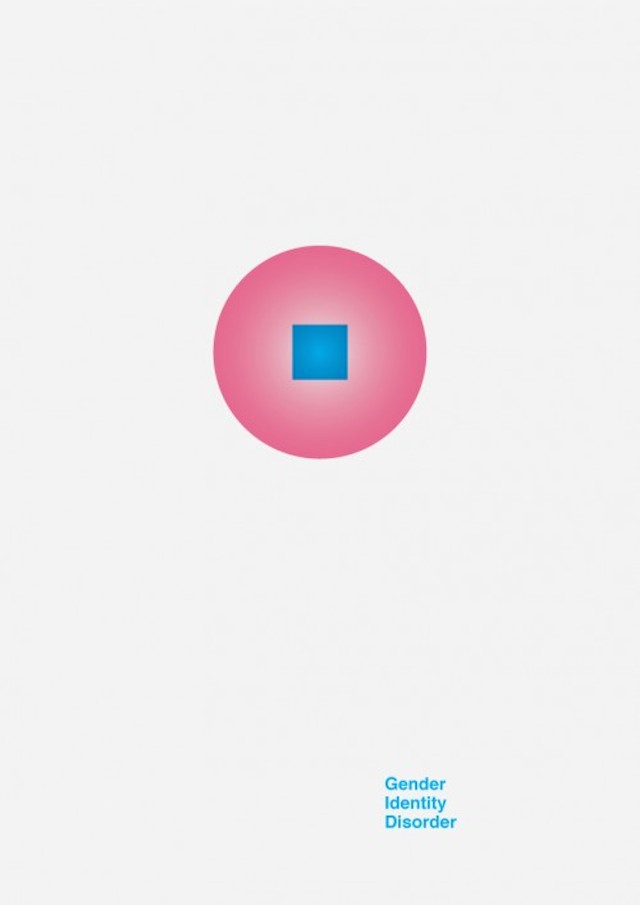

Like Christian Stoll who has put colors on psychology and emotions, Designer Patrick Smith managed to put graphic symbols on complex mental disorders. Through 7 minimalist posters and respecting precise color codes, we can decrypt the feelings of lack of understanding, division and isolation in certain psychological diseases.